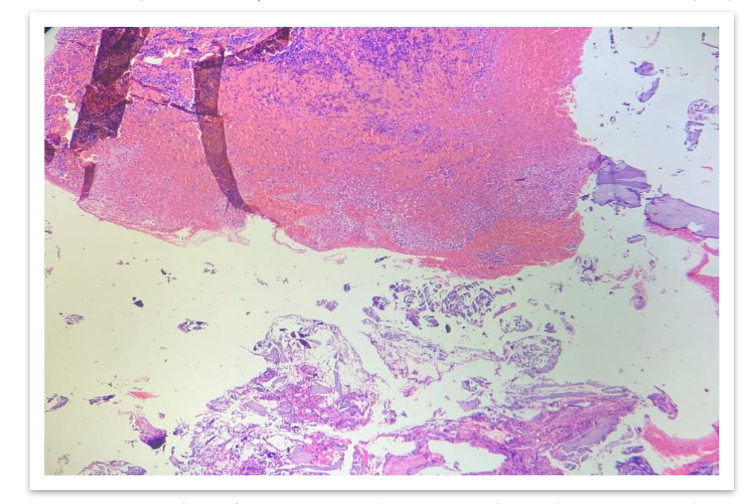

On gross examination, we received multiple grey brown to grey black soft tissue fragments altogether measuring 0.5cc, all the tissue was embedded in paraffin. Before grossing, tissue samples were fixed in 10% buffered neutral formalin. Sections were processed and stained with hematoxylin and eosin.

Microscopically, loosely arranged clusters of plasmacytoid cells, some are seen embedded in an eosinophilic osteoid like stroma. Few areas showed neutrophilic infiltration, spicules of degenerated bone, areas of haemorrhage and few bundles of striated muscle fibres. It was reported as Plasma cell malignancy- probably multiple myeloma (Non secretory type) as serum protein electrophoresis was normal.